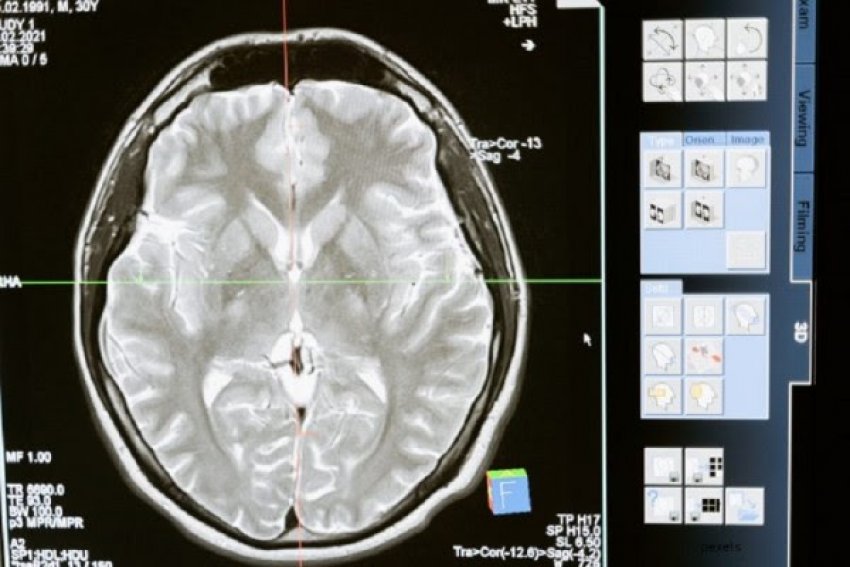

Betim GashiShkencëtarët britanikë kanë gjetur një ilaç që mund ta ndalë kancerin dhe në këtë mënyrë ta detyrojë atë të tërhiqet. Ky sukses mund të jetë përparimi i parë në trajtimin e tumoreve të trurit në dy dekadat e fundit.

Shkencëtarët nga Kolegji Mbretëror në Londër kryen teste te minjtë me glioblastomë (GBM) – një nga format më agresive të kancerit të trurit. Brejtësve iu dha një ilaç eksperimental që i privoi ata nga aminoacidi argininë – një lëndë ushqyese jetike që tumoret përdorin për t’u rritur.

Në një studim të ri të botuar në Journal of Clinical Investigation, minjtë e trajtuar jetuan rreth 47 ditë, pothuajse dy herë më shumë se ata të pa trajtuar, të cilët mbijetuan 27 ditë. Për krahasim, disa minj iu nënshtruan radioterapisë ose rrezatimit. Ata jetuan mesatarisht 37 ditë.

Por kur ilaçi i ri u kombinua me radioterapi, të gjithë minjtë kaluan në remision dhe jetuan pa kancer për rreth një vit përpara se të vriteshin.

GBM është lloji më i zakonshëm i tumorit primar të trurit të shkallës së lartë tek të rriturit, dhe është gjithashtu më agresiv dhe vdekjeprurës. Më pak se një për qind e pacientëve me GBM jetojnë më shumë se dhjetë vjet, dhe për shumë prognoza është vetëm 12 muaj.